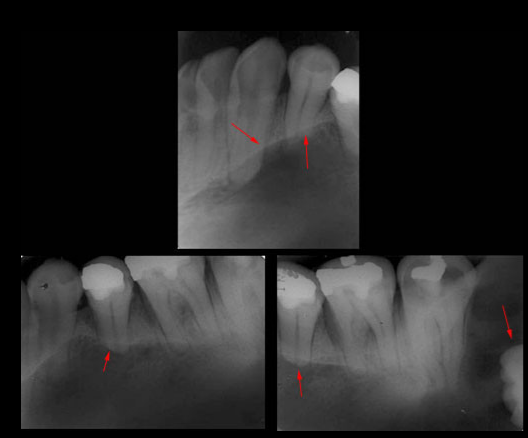

Caso N° 207: AMELOGÉNESIS IMPERFECTA

Paciente de sexo masculino de 40 años de edad acude a la consulta radiológica previo tratamiento protésico. Al examen intraoral se observó una alteración en el color de los dientes notándose amarillento parduzcos así como de la morfología coronal de las piezas dentarias de forma generalizada, además, de presentar superficies de forma irregular. En la radiografía panorámica digital observamos (Fig.1) una disminución generalizada en el espesor del esmalte dentario así como la ausencia de cúspides. En las radiografías periapicales (Fig. 2) confirmamos las características antes descritas.